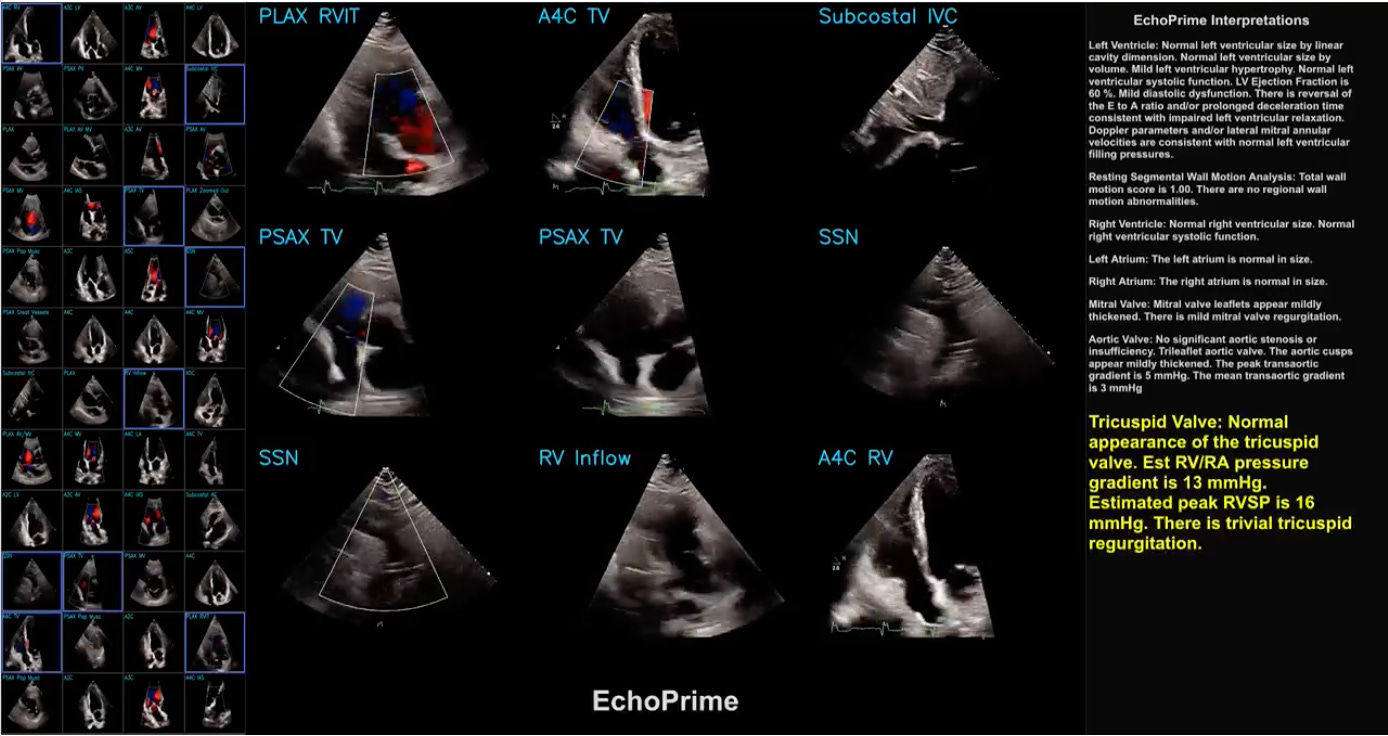

EchoPrime is a multi-view, view-informed, video-based vision-language foundation model trained on over 12 million video-report pairs.

EchoPrime uses contrastive learning to train a unified embedding model for all standard views in a comprehensive echocardiogram study with a representation of both rare and common diseases and diagnoses. EchoPrime then utilises view-classification and a view-informed anatomic attention model to weight video-specific interpretations that accurately maps the relationship between echocardiographic views and anatomical structures.

With retrieval-augmented interpretation, EchoPrime integrates information from all echocardiogram videos in a comprehensive study and performs holistic, comprehensive clinical echocardiography interpretation. In datasets from two independent healthcare systems, EchoPrime achieves state-of-the-art performance on 23 diverse benchmarks of cardiac form and function, surpassing the performance of both task-specific approaches and prior foundation models.

Following rigorous clinical evaluation, EchoPrime can assist physicians in the automated preliminary assessment of comprehensive echocardiography.